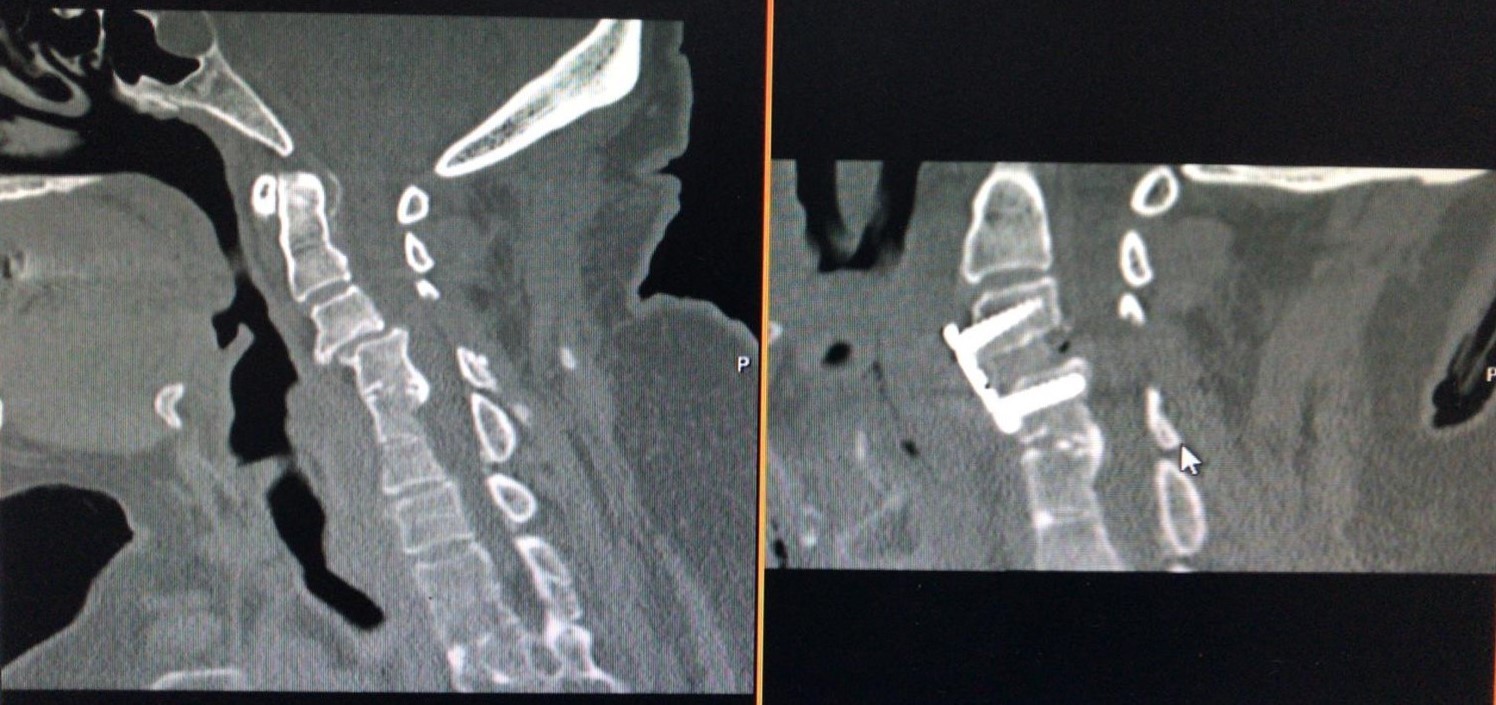

Figure 3.Computerized tomography scans of a Yilmaz-Yucesoy Classification System Grade 4 patient who underwent anterior cervical discectomy and fusion with cervical cage and plate.

Computerized tomography scans of a Yilmaz-Yucesoy Classification System Grade 4 patient who underwent anterior cervical discectomy and fusion with cervical cage and plate.